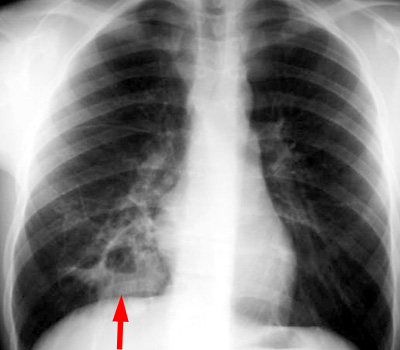

CXR demonstrating a consolidation with cavitation in the medial right lower lobe. |